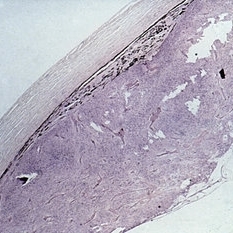

Slide 7-12

Feb 25 2019 by Lancaster Course in Ophthalmology

Pingueculum showing masses of fragmented fibers resembling actinic elastosis.

Condition/keywords: actinic elastosis, pinguecula